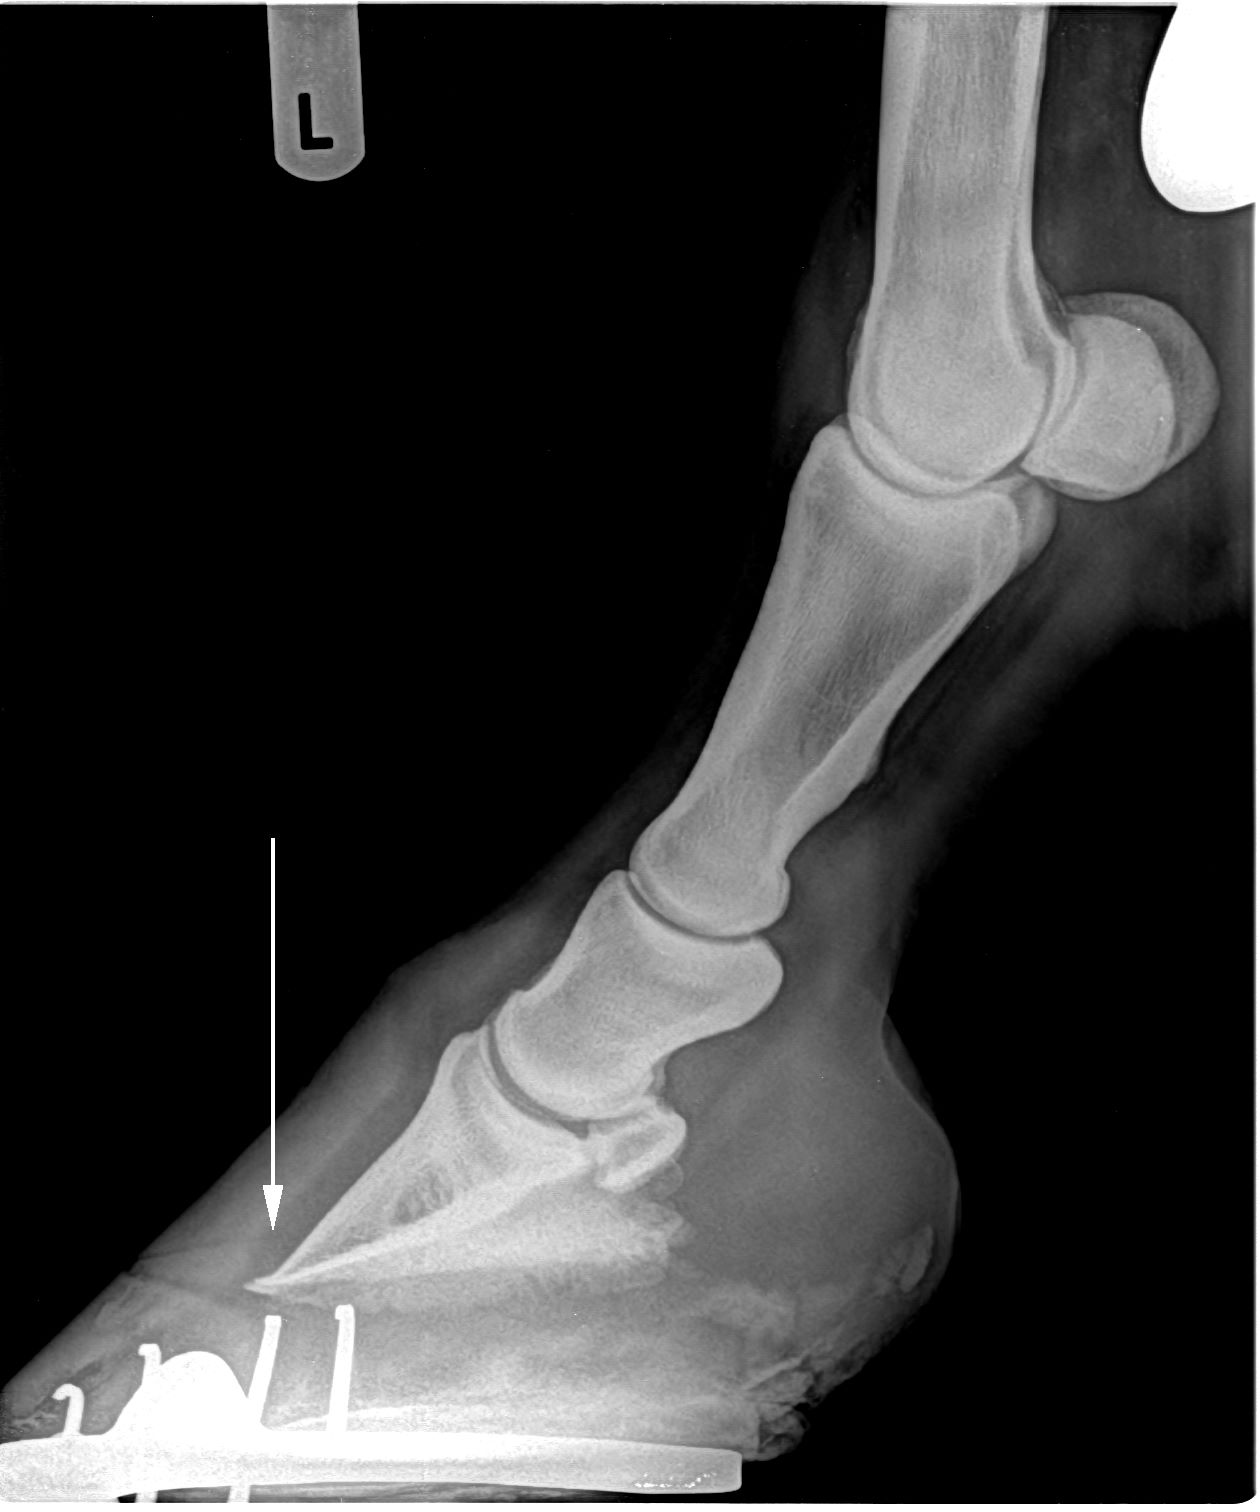

Die Lahmheit eines Pferdes gehört zu den Hauptursachen der Leistungsminderung eines Pferdes. Die Röntgenuntersuchung zählt neben der Ultraschall-, Computertomographie oder Szintigraphieuntersuchung als ein entscheidendes Instrument zur Diagnose, Behandlung und Prognose von Lahmheiten beim Pferd. Aber auch im Rahen einer Ankaufsuntersuchung kann die Röntgenuntersuchung eingesetzt werden, um eventuelle Mängel oder Krankheiten zu erkennen. Die Röntgenuntersuchung ist eine einfache und schnell durchführbare Untersuchung in Ihrem Stall. Bei gestressten Pferden und/oder zur Optimierung der Aufnahmequalität können die Pferde eine kurze Sedierung bekommen. Durch die digitale Röntgentechnik, im Vergleich zur „alten“ konventionellen Röntgentechnik, können die Bilder unmittelbar vor Ort entwickelt und am Laptop ausgewertet werden bzw. kann das Röntgenbild nachbearbeitet werden (Bildoptimierung). In vielen Fällen erfolgt dann eine Zusammenarbeit mit Ihrem Schmied, um die Lahmheit zu verringern oder zu beheben.

Chronische Hufrehe

Sehnenverkalkung

Griffelbeinfraktur

Krongelenkarthrose (sog. Schale)